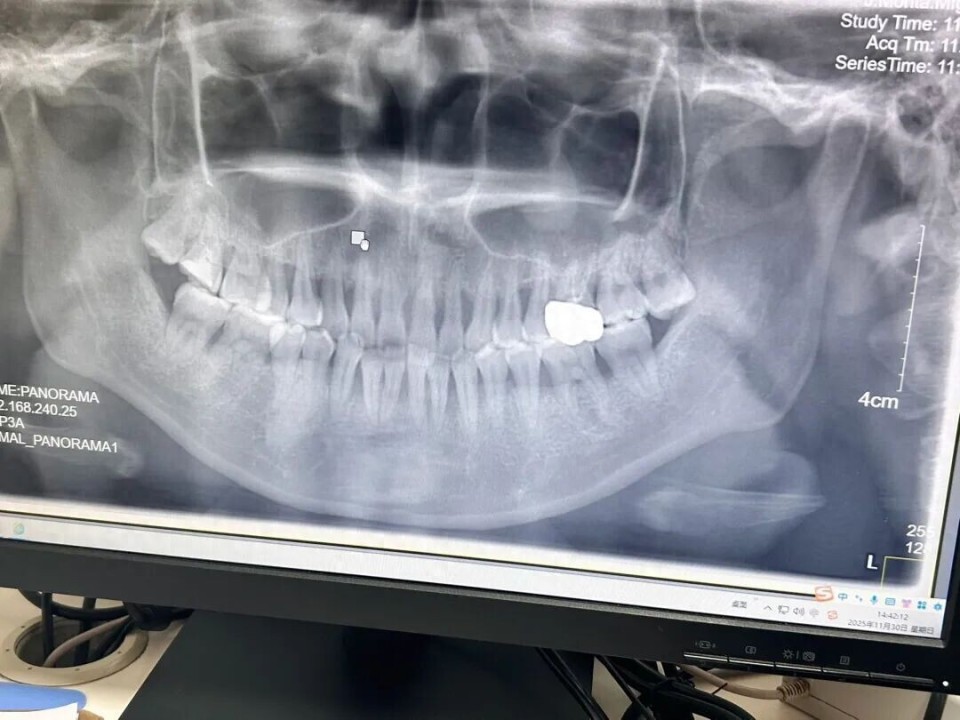

2025年11月,赵玥于武汉市一家三甲牙齿专科医院拍摄的牙片 图/受访者提供